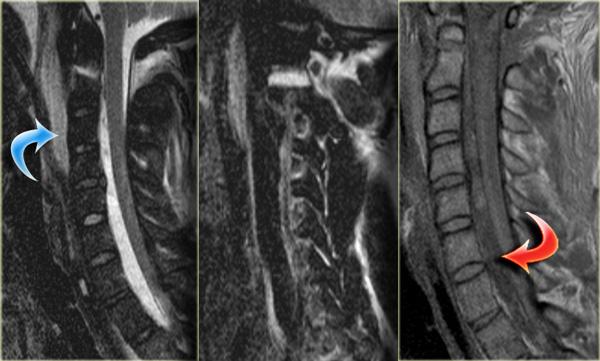

Có hai loại tổn thương tủy sống:

- Không xuất huyết, chỉ biểu hiện tăng tín hiệu trên MRI do phù nề.

- Xuất huyết với các vùng giảm tín hiệu nằm trong vùng phù nề.

Có mối tương quan chặt chẽ giữa chiều dài vùng phù nề tủy sống và kết cục lâm sàng.

Tuy nhiên, yếu tố quan trọng nhất là có hay không có xuất huyết, vì tổn thương tủy sống xuất huyết có tiên lượng cực kỳ xấu.

Biểu đồ bên trái thể hiện tỷ lệ phục hồi vận động của bệnh nhân chỉ có phù nề (màu xanh) so với phù nề kèm xuất huyết tủy sống (màu đỏ).

Tỷ lệ phục hồi vận động chỉ tính cho chi dưới.

Tổn thương tủy sống trung tâm ở bệnh nhân chấn thương tăng duỗi trên nền thoái hóa và hẹp ống sống có sẵn.

Các hội chứng tủy sống (2):

Hội chứng tủy sống trung tâm (Central cord syndrome)

- Hội chứng tủy không hoàn toàn phổ biến nhất.

- Thường gặp ở người cao tuổi có thoái hóa cột sống nền hoặc người trẻ với chấn thương duỗi nặng (hình minh họa).

- Thiếu hụt vận động chi trên nặng hơn chi dưới, do bó vỏ-gai chi dưới nằm ở phần bên của tủy sống.